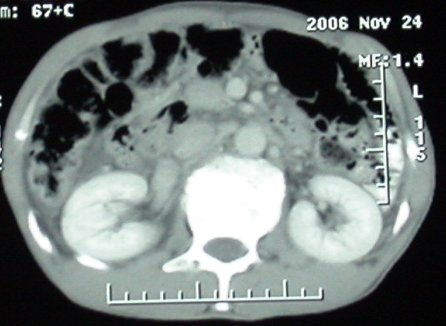

增强ct所见【动脉增强期】

增强ct所见

门脉主干及肠系膜上静脉近端明显增粗,尤其前者呈等低混杂密度,增强后周围见轻度环形强化。明显占位效应。肝内外胆管见大量气体影。胆囊明显增大。

影像表现:胆囊扩张、肝内胆管不扩张,且见肝脏内树枝样气体影;十二指肠后方等密度占位,中心有不规则囊变区。增强实质部分轻度强化。下部腔静脉未强化------有栓子吗?